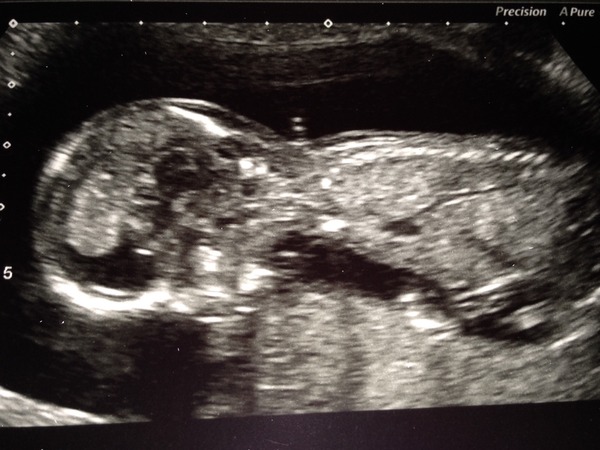

Opinions on skull theory and its accuracy please x

Hi I'm 14 weeks today and rather curious about skull theory and how accurate it is as we don't have our sexing scan for another 6 weeks and the suspense is killing me confused Any gender predictions are more than welcome smile

I think it looks like a girl skull!